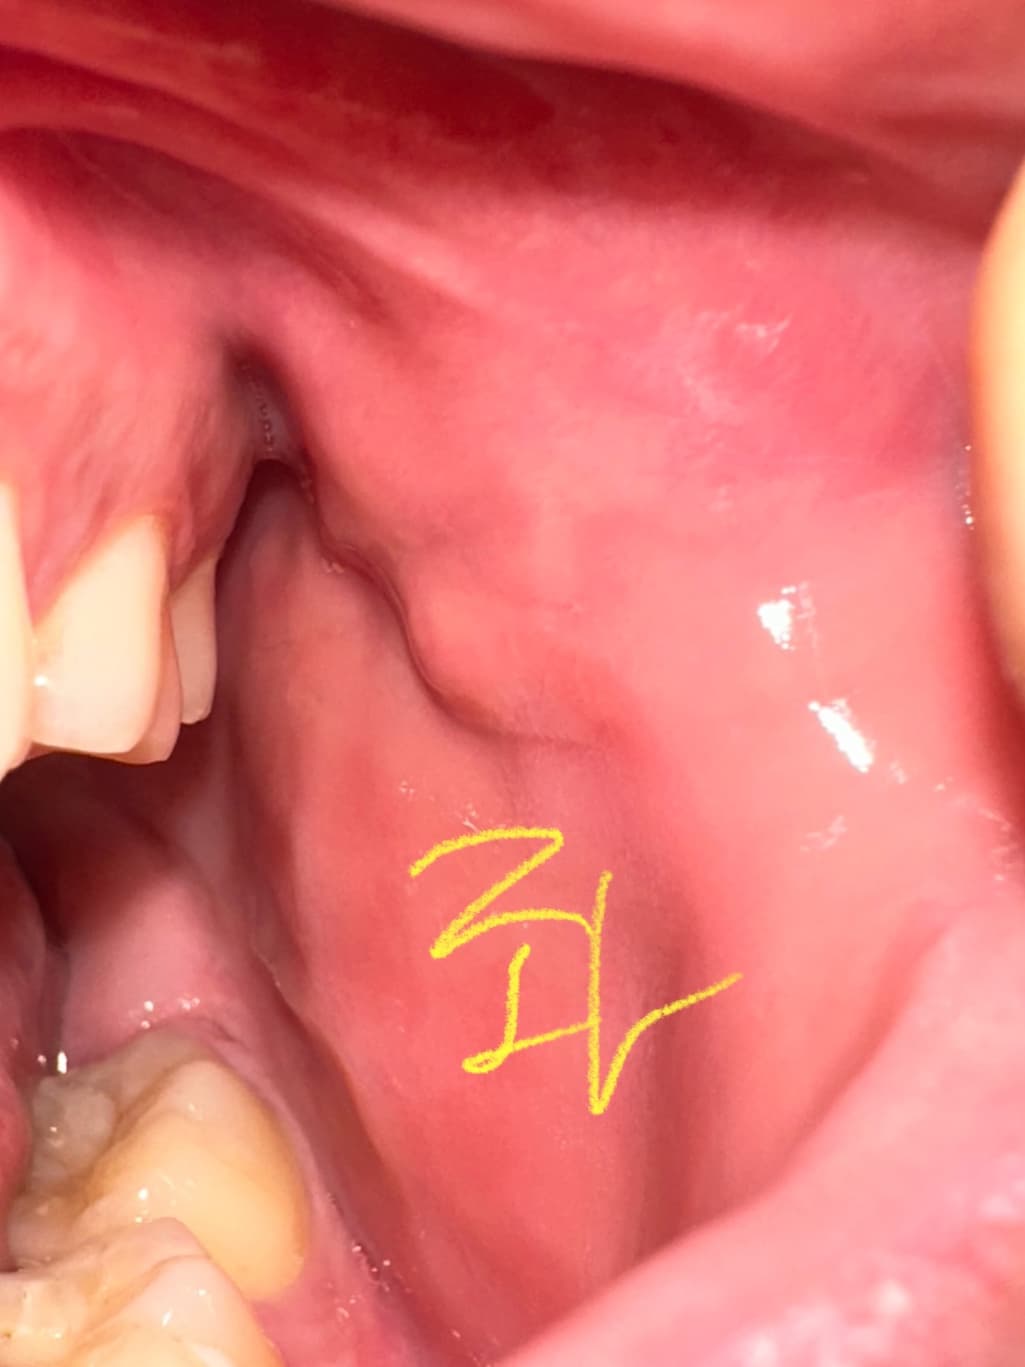

구강내 우측 상당 어금니 부분 옆 볼살에 이질감이 느껴집니다

안냥하세요 평소에도 좌측과 우측 동일하게 혹 비스무리흔디 잡히고 그랬었습니다 다만, 이틀 전 부터 우측 부분이 붓고 평소보다 살짝 더 심하게 느껴지는 것 같았슺니드 이게 정살일가료? 참고로 흡연 11년 하루 8개이며 나으ㅡㅡㅡㄷ

• 3번 째 사진

볼살이 치아에 씹혀서 부종이 생긴거 같습니다. 큰 문제가 잇는건 아니니 너무 걱정하지마세요.

사진으로는 특별한 문제가 보이진 않습니다. 점막 조직에 자극이 많이 되었을 경우 불편한 감각이 있을 수 있으니 흡연으로 인한 점막 조직의 자극을 줄이는 것이 좋을 것으로 생각됩니다.

해당 부분은 단순히 볼이 씹혀서 그럴 가능성이 높습니다. 치과가서 검사 받아보심이 좋아보입니다.